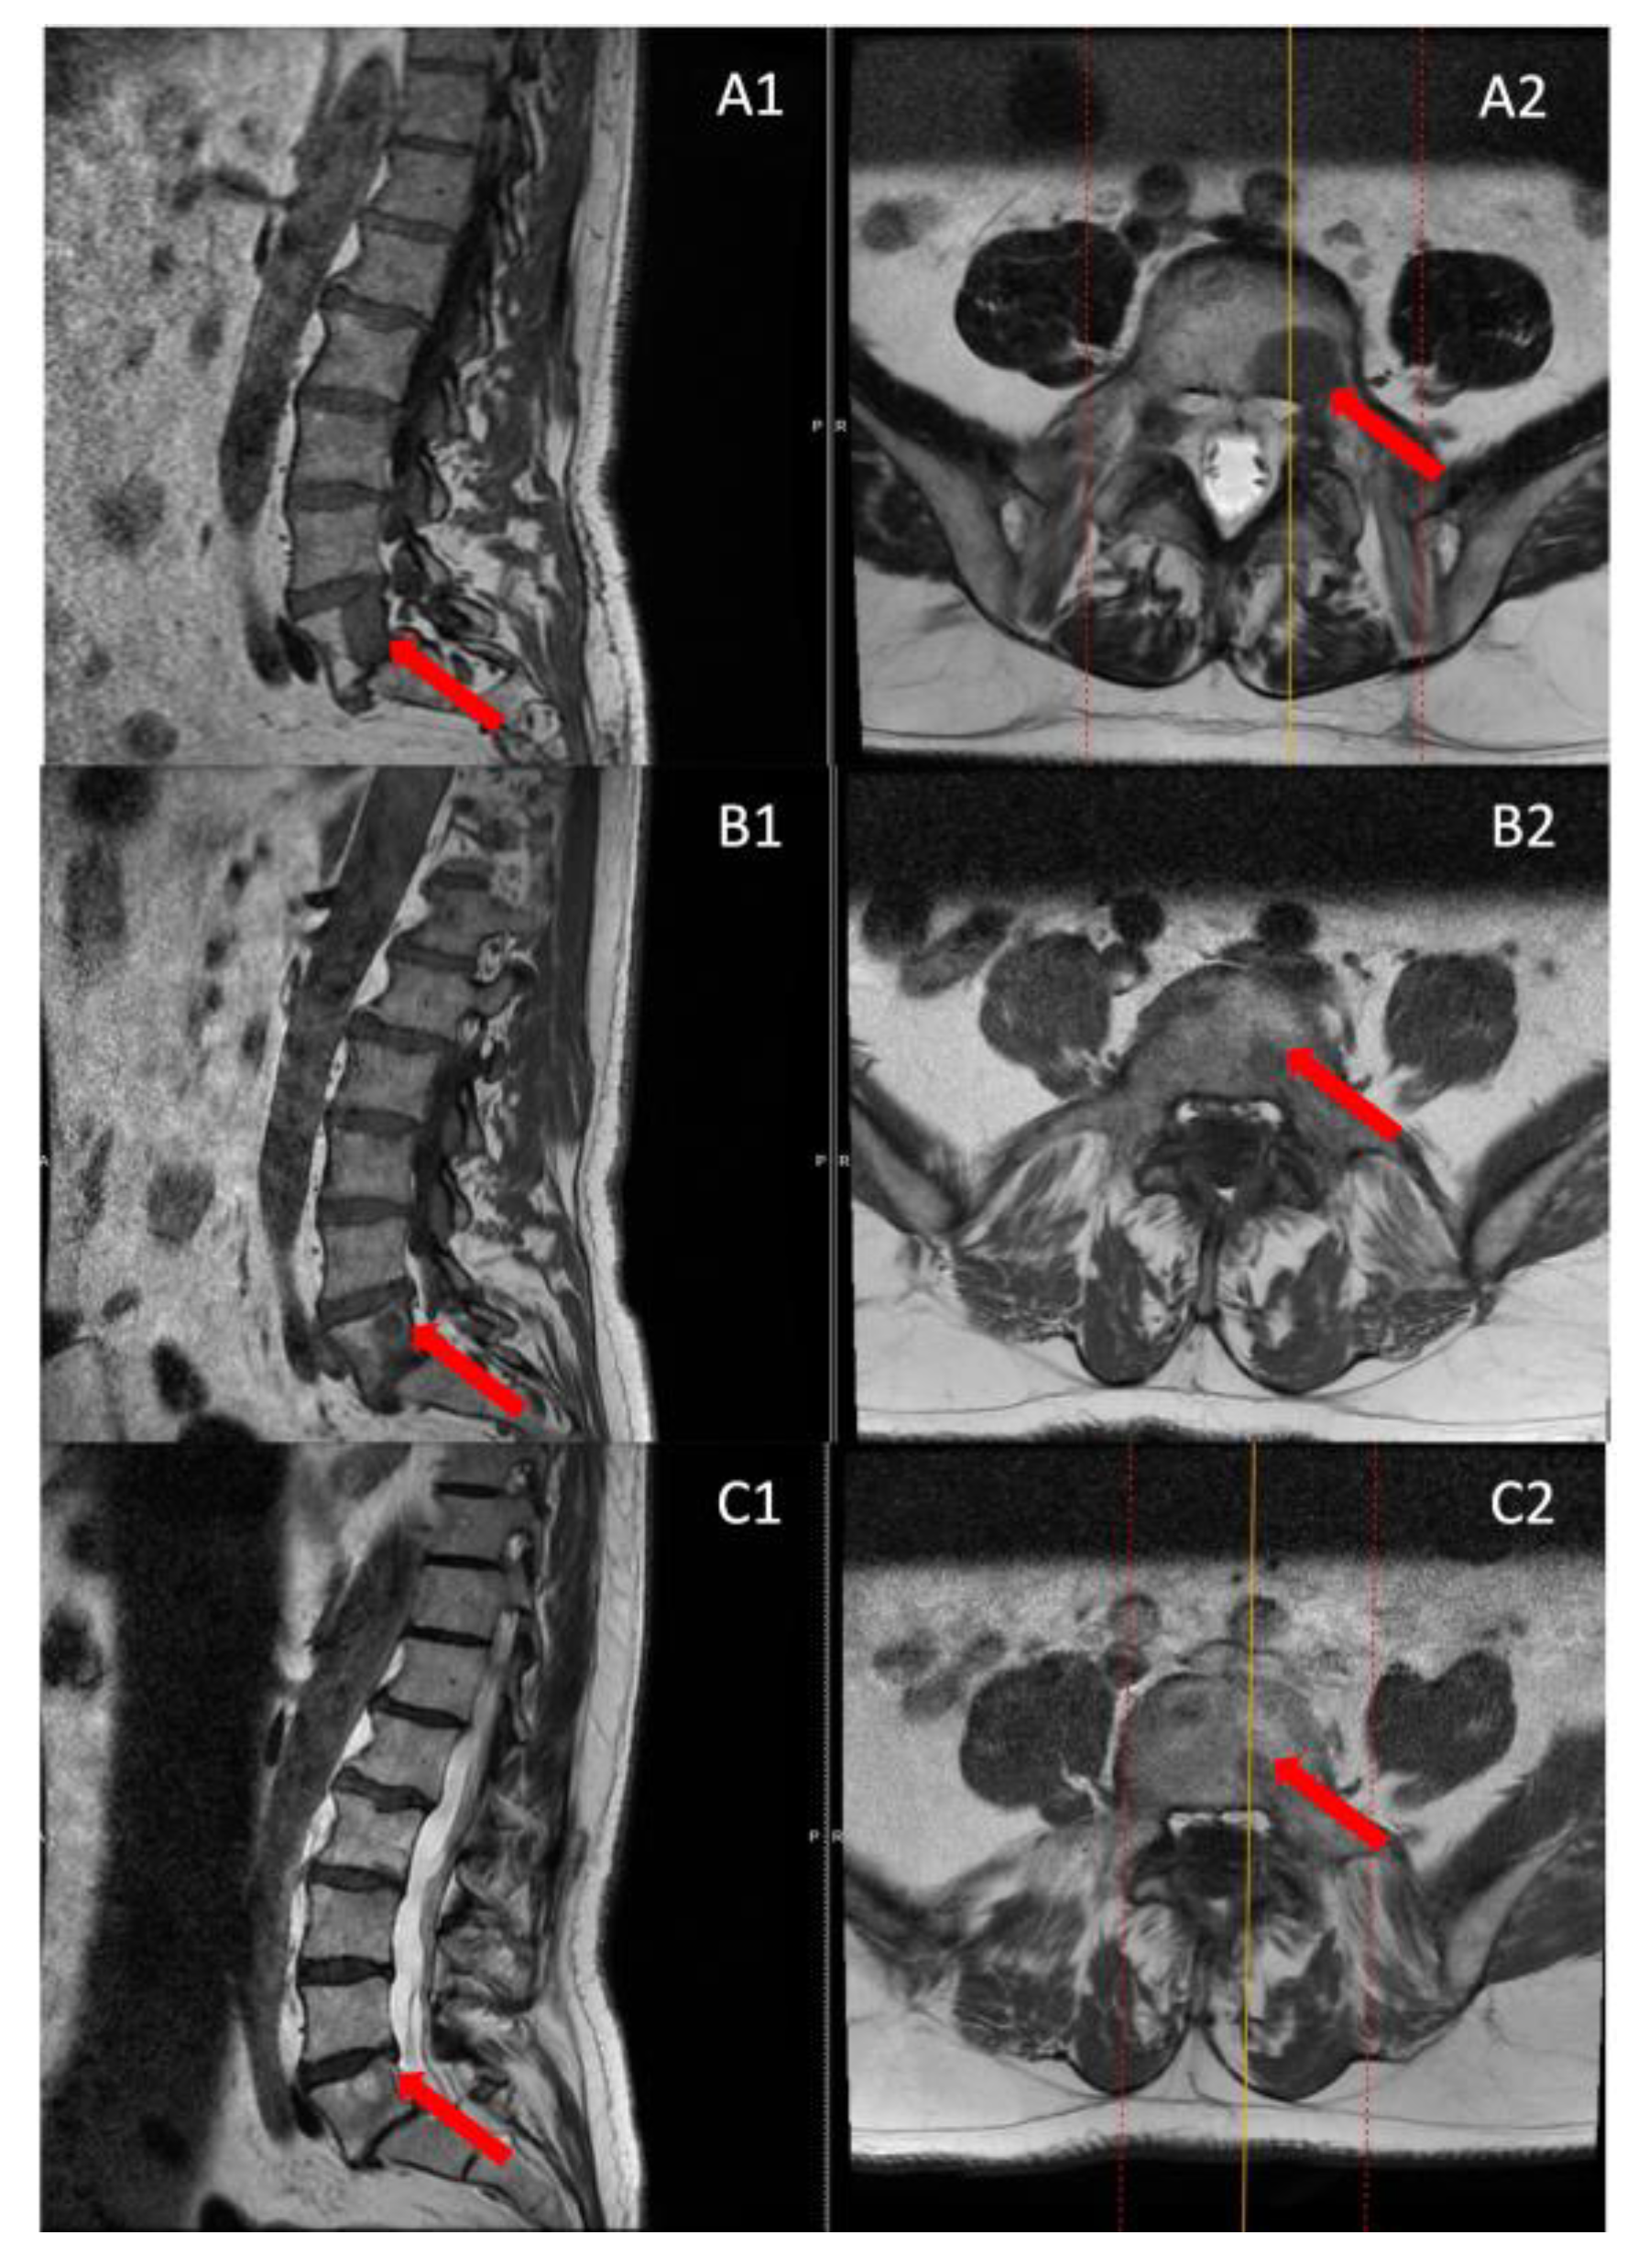

Interestingly, the tumor was visible on CT in only one patient, but MRI provided more accurate tumor dimensions (Table 2). MRI successfully revealed the tumors in all four patients (Figure 4). These patients presented with localized pain that did not radiate to the legs.

Figure 5. MRI scans before surgery (A), 6 months post-surgery (B), and 12 months post-surgery (C), were examined in both sagittal (1) and axial sections (2). The red arrow shows the lesion location.

The follow-up MRI scans conducted at both the 6th and 12th months post-surgery revealed no indications of tumor recurrence in any of the patients, and a reduction in the size of the entire lesion was observed compared to pre-surgery (Figure 5).